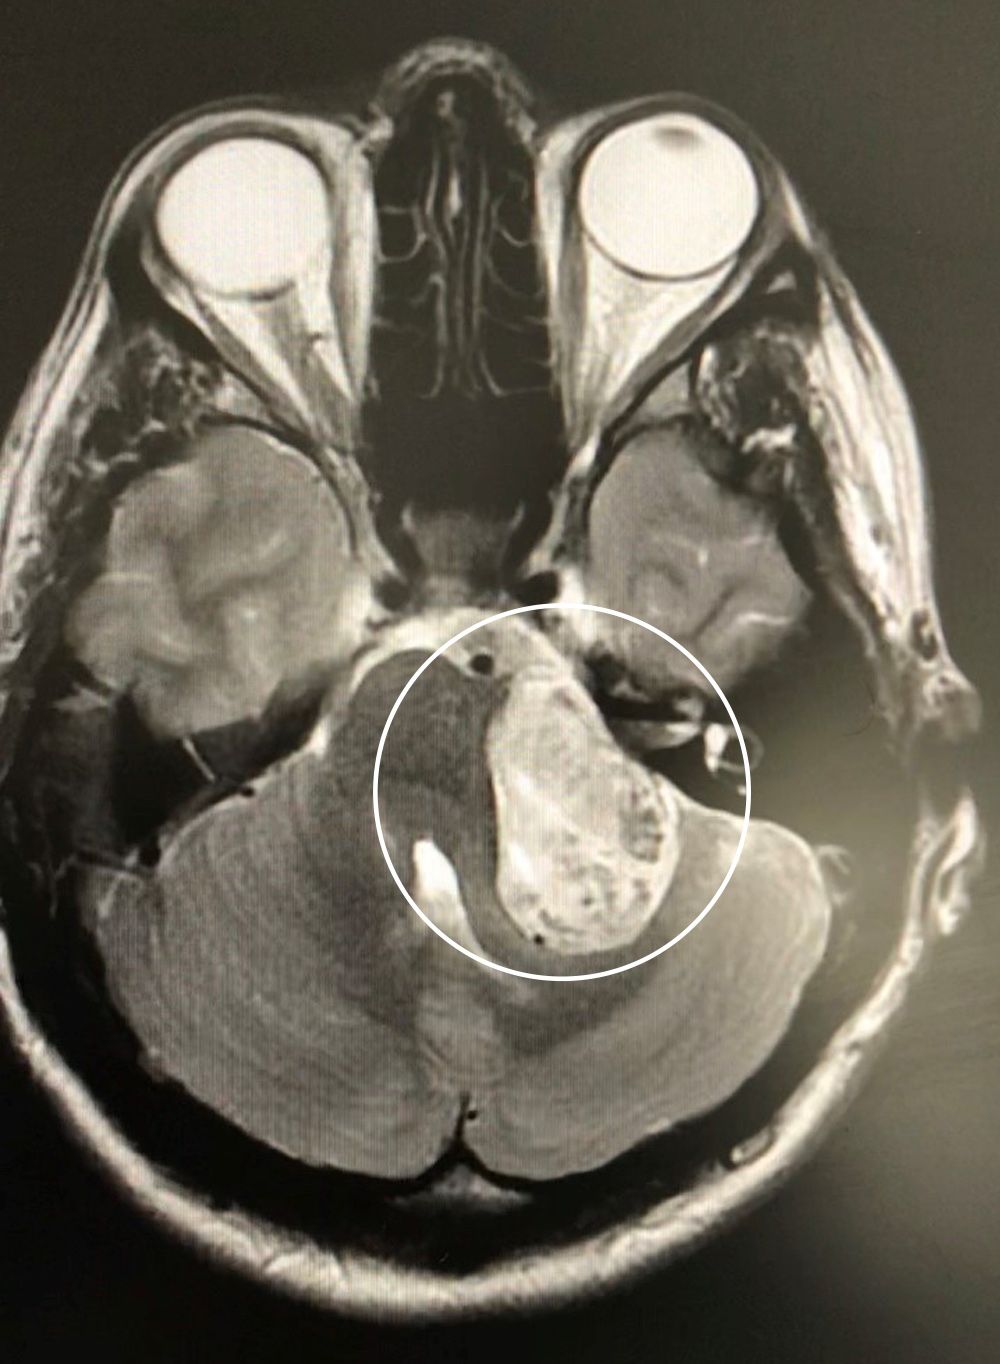

But, out jogging with her local running group in November 2019, she suddenly lost her balance, crashing into a garden wall—leading to further investigations which identified a 4cm tumor, pressing on the nerve connecting her inner ear to her brain.

In March, Emily used her private health insurance to have an MRI scan at Peterborough's Fitzwilliam Hospital where, to her horror, she was told she had a tumor the size of a golf ball on the left side of her brain, pressing against the nerves controlling hearing and balance.

Two days later, she was officially diagnosed with an acoustic neuroma—a benign tumor that grows slowly over the course of many years—affecting around two in 100,000 people in the UK annually, according to the charity British Acoustic Neuroma Association (BANA).